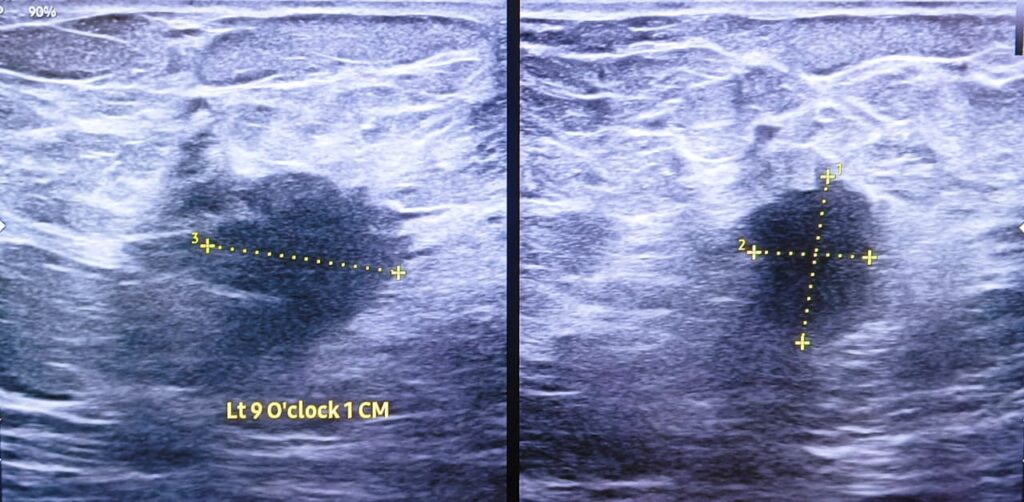

The lesion that the patient was referring to, was a harmless lump of breast, also known as a breast mouse. Another less than one centimetre sized similar focus was noted in the medial upper quadrant.

A highly suspicious lesion in the same breast was noted medial to the nipple. It was only about less than two centimetres in size, but had all the malicious sonographic characteristics.

The disease was caught early, before it could spread all over the body and grow incurable.

Breast cancer is the most common cancer in women. It causes millions of deaths annually all over the world. Early detection and timely diagnosis with comprehensive management is essential to avert breast cancer deaths.